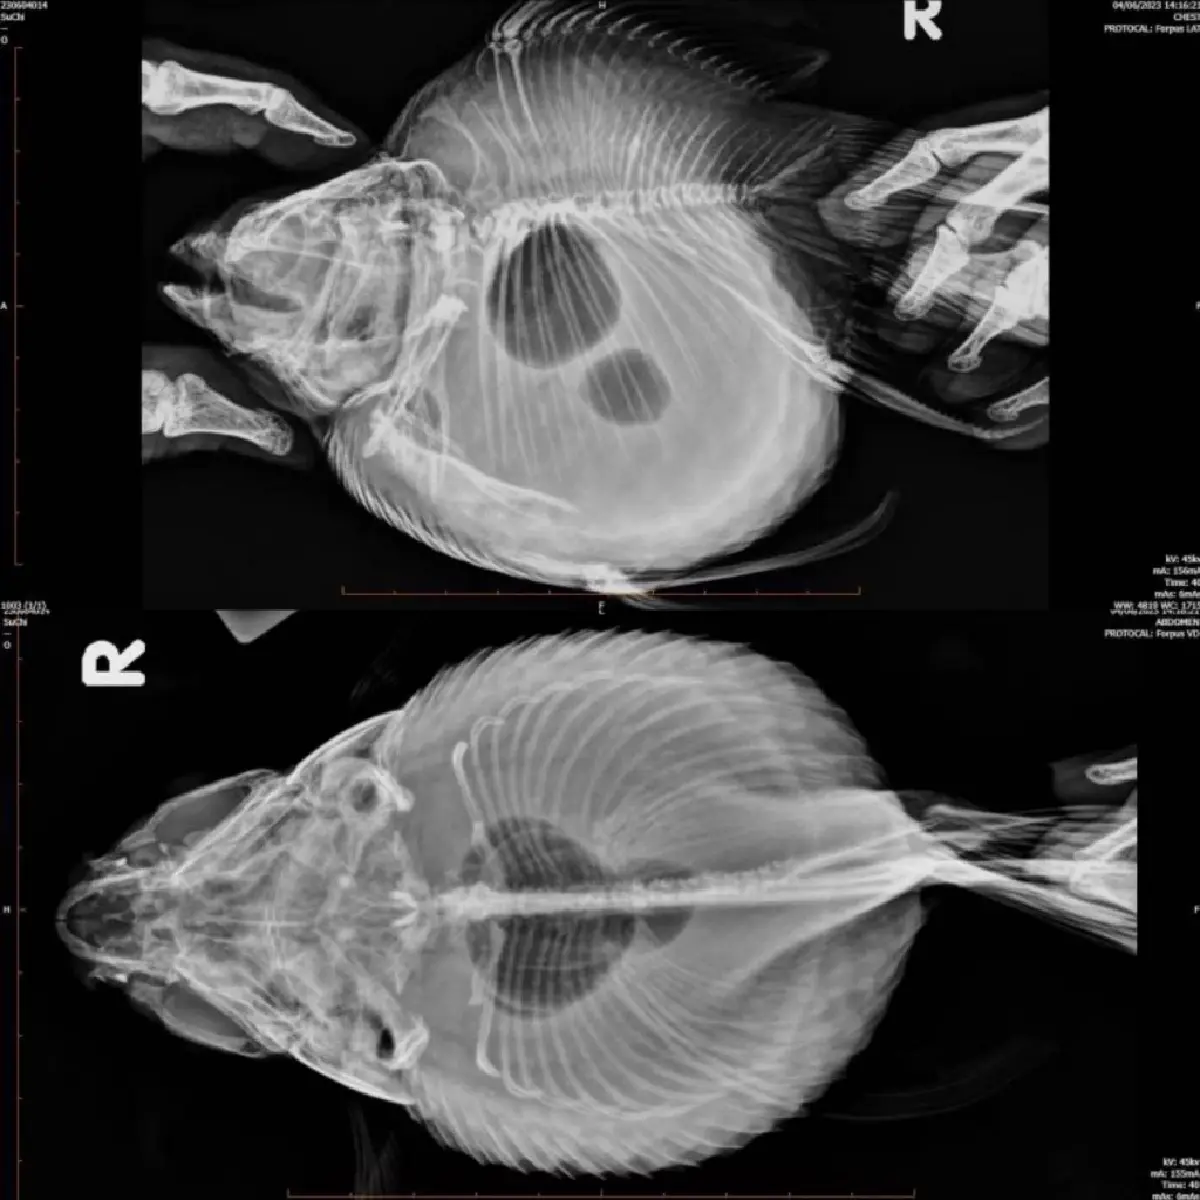

นอกจากนี้ ฟูจิฟิล์มยังนำเสนอระบบเอกซเรย์ประสิทธิภาพสูงที่มาพร้อมฟังก์ชันการทำงานที่หลากหลาย สามารถตอบโจทย์การใช้งานที่ยืดหยุ่นเพื่อการพยาบาลสัตว์หลากหลายชนิดในโรงพยาบาลและคลินิกรักษาสัตว์ อาทิ FDR Smart X โซลูชันระบบเอกซเรย์ ที่ชูระบบการทำงานได้ทั้งแบบติดตั้งพื้นและแบบแขวนติดเพดาน

ทำให้ถ่ายภาพรังสีได้อย่างคมชัดและครอบคลุมทุกมุมตามที่ต้องการเพื่อการวินิจฉัยที่แม่นยำที่สุด พร้อมด้วยฟีเจอร์ที่ใช้งานง่ายและการตั้งค่าที่สะดวก รวดเร็ว พร้อมคุณภาพของภาพที่ชัดเจนทุกรายละเอียด ออกแบบมาเพื่อการทำงานที่คล่องตัวสำหรับบุคลากรทางการแพทย์ ด้วยเทคโนโลยีการประมวลผลภาพคุณภาพสูงในแผ่นรับภาพ FDR D-EVO II ที่สามารถตรวจพบความผิดปกติภายในร่างกายและอวัยวะของสัตว์ซึ่งมีขนาดและลักษณะทางกายภาพที่แตกต่างจากมนุษย์ได้อย่างแม่นยำ

พร้อมเตียงเอกซเรย์ขนาดใหญ่ที่สามารถรองรับการเอกซเรย์สัตว์ได้ครอบคลุมตั้งแต่ขนาดเล็ก ขนาดกลาง และขนาดใหญ่ได้อย่างมีประสิทธิภาพ ไม่ว่าจะเป็นสัตว์เลี้ยงอย่าง สุนัข และแมว หรือสัตว์ Exotic อาทิ นก กระรอก กระต่าย กิ้งก่า กบ เต่า ไปจนถึงสัตว์ป่าขนาดใหญ่อย่างสิงโต